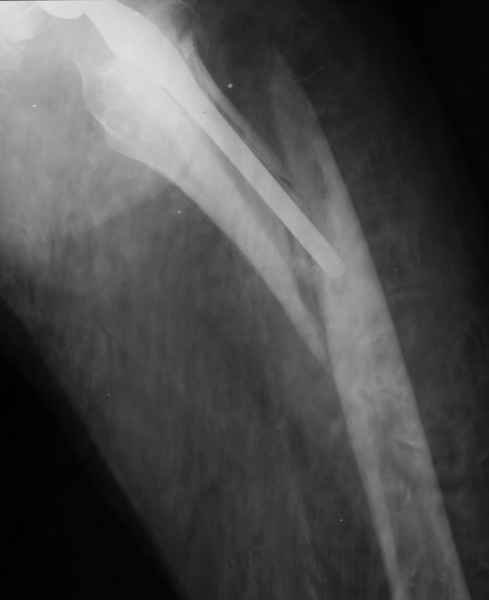

Весь проксимальный отдел бедренной кости ведь смещен относительно ножки эндопротеза? Значит менять ножку нужно. К тому же, если думать об удлинении ножки стержнем, место стыка получится как раз в области поперечной части перелома и о стабильности такой конструкции вряд ли можно будет думать. Так что - длинная ревизионная ножка с остеосинтезом. Может быть и серкляжей будет достаточно если перелом проксимальной части не оскольчатый (по снимкам не очень понятно).

Закрытый остеосинтез-удлинение ножки (подход далеко не общепринятый, и пока даже не общеизвестный)- наименее инвазивный вариант, который обеспечивает немедленное восстановление опороспособности. Конечно, хотелось бы, чтобы эта операция решила проблему окончательно, т.е. в

ближайшие годы других больших операций не потребовалось бы.

ножка просела немного (вопрос, много - это сколько?)перечисленные проблемы - не самое важное сейчас, на них можно закрыть глаза. Ножка явно нестабильна, проксимальный отломок с б/вертелом к гвоздю не прицепить, срастется ли он с ножкой

Можно уверенно рассчитывать на сращение фрагментов бедра между собой. Можно ли рассчитывать на реинтеграцию имеющейся ножки в проксимальном отделе - действительно вопрос открытый. Но во всяком случае ножка будет заметное время стабильной за счет дистальной фиксации. Будет ли это время достаточно на всю оставшуюся жизнь пациента - трудно предугадать.

Но, как Александр Виноградский справедливо заметил, после сращения бедра появляется возможность поставить даже обычную ножку большего размера.

1.Остеосинтез на ножке. Мне кажется, что применительно к этому случаю малоперспективный вариант. Синтез хорош, когда можно его выполнить в малоинвазивном исполнении и достигнуть стабильности. Действительно, если ножка б/цементной фиксации после этого не будет иметь фиксации, то ревизия не будет иметь проблем. В представленном случае стабильность синтеза сомнительная, а проведение доп.иммобилизации приведет к контрактуре суставов.

2. Применение ножки дистальной фиксации, мы отдаем предпочтение ножке Вагнера с фиксацией проксимального отдела на ножке. Более травматичное вмешательство, но при стабильной фиксации ножки реабилитация идет в обычном режиме.